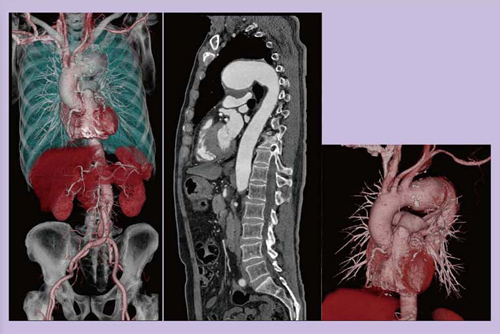

図9は,以前にCABGを施行している胸部大動脈瘤(TAA)の術前症例である。スキャンタイム1.53秒で,広範囲の画像を取得することができ,手術に必要な情報を提供することが可能であった。

図9 65歳,女性,TAA術前